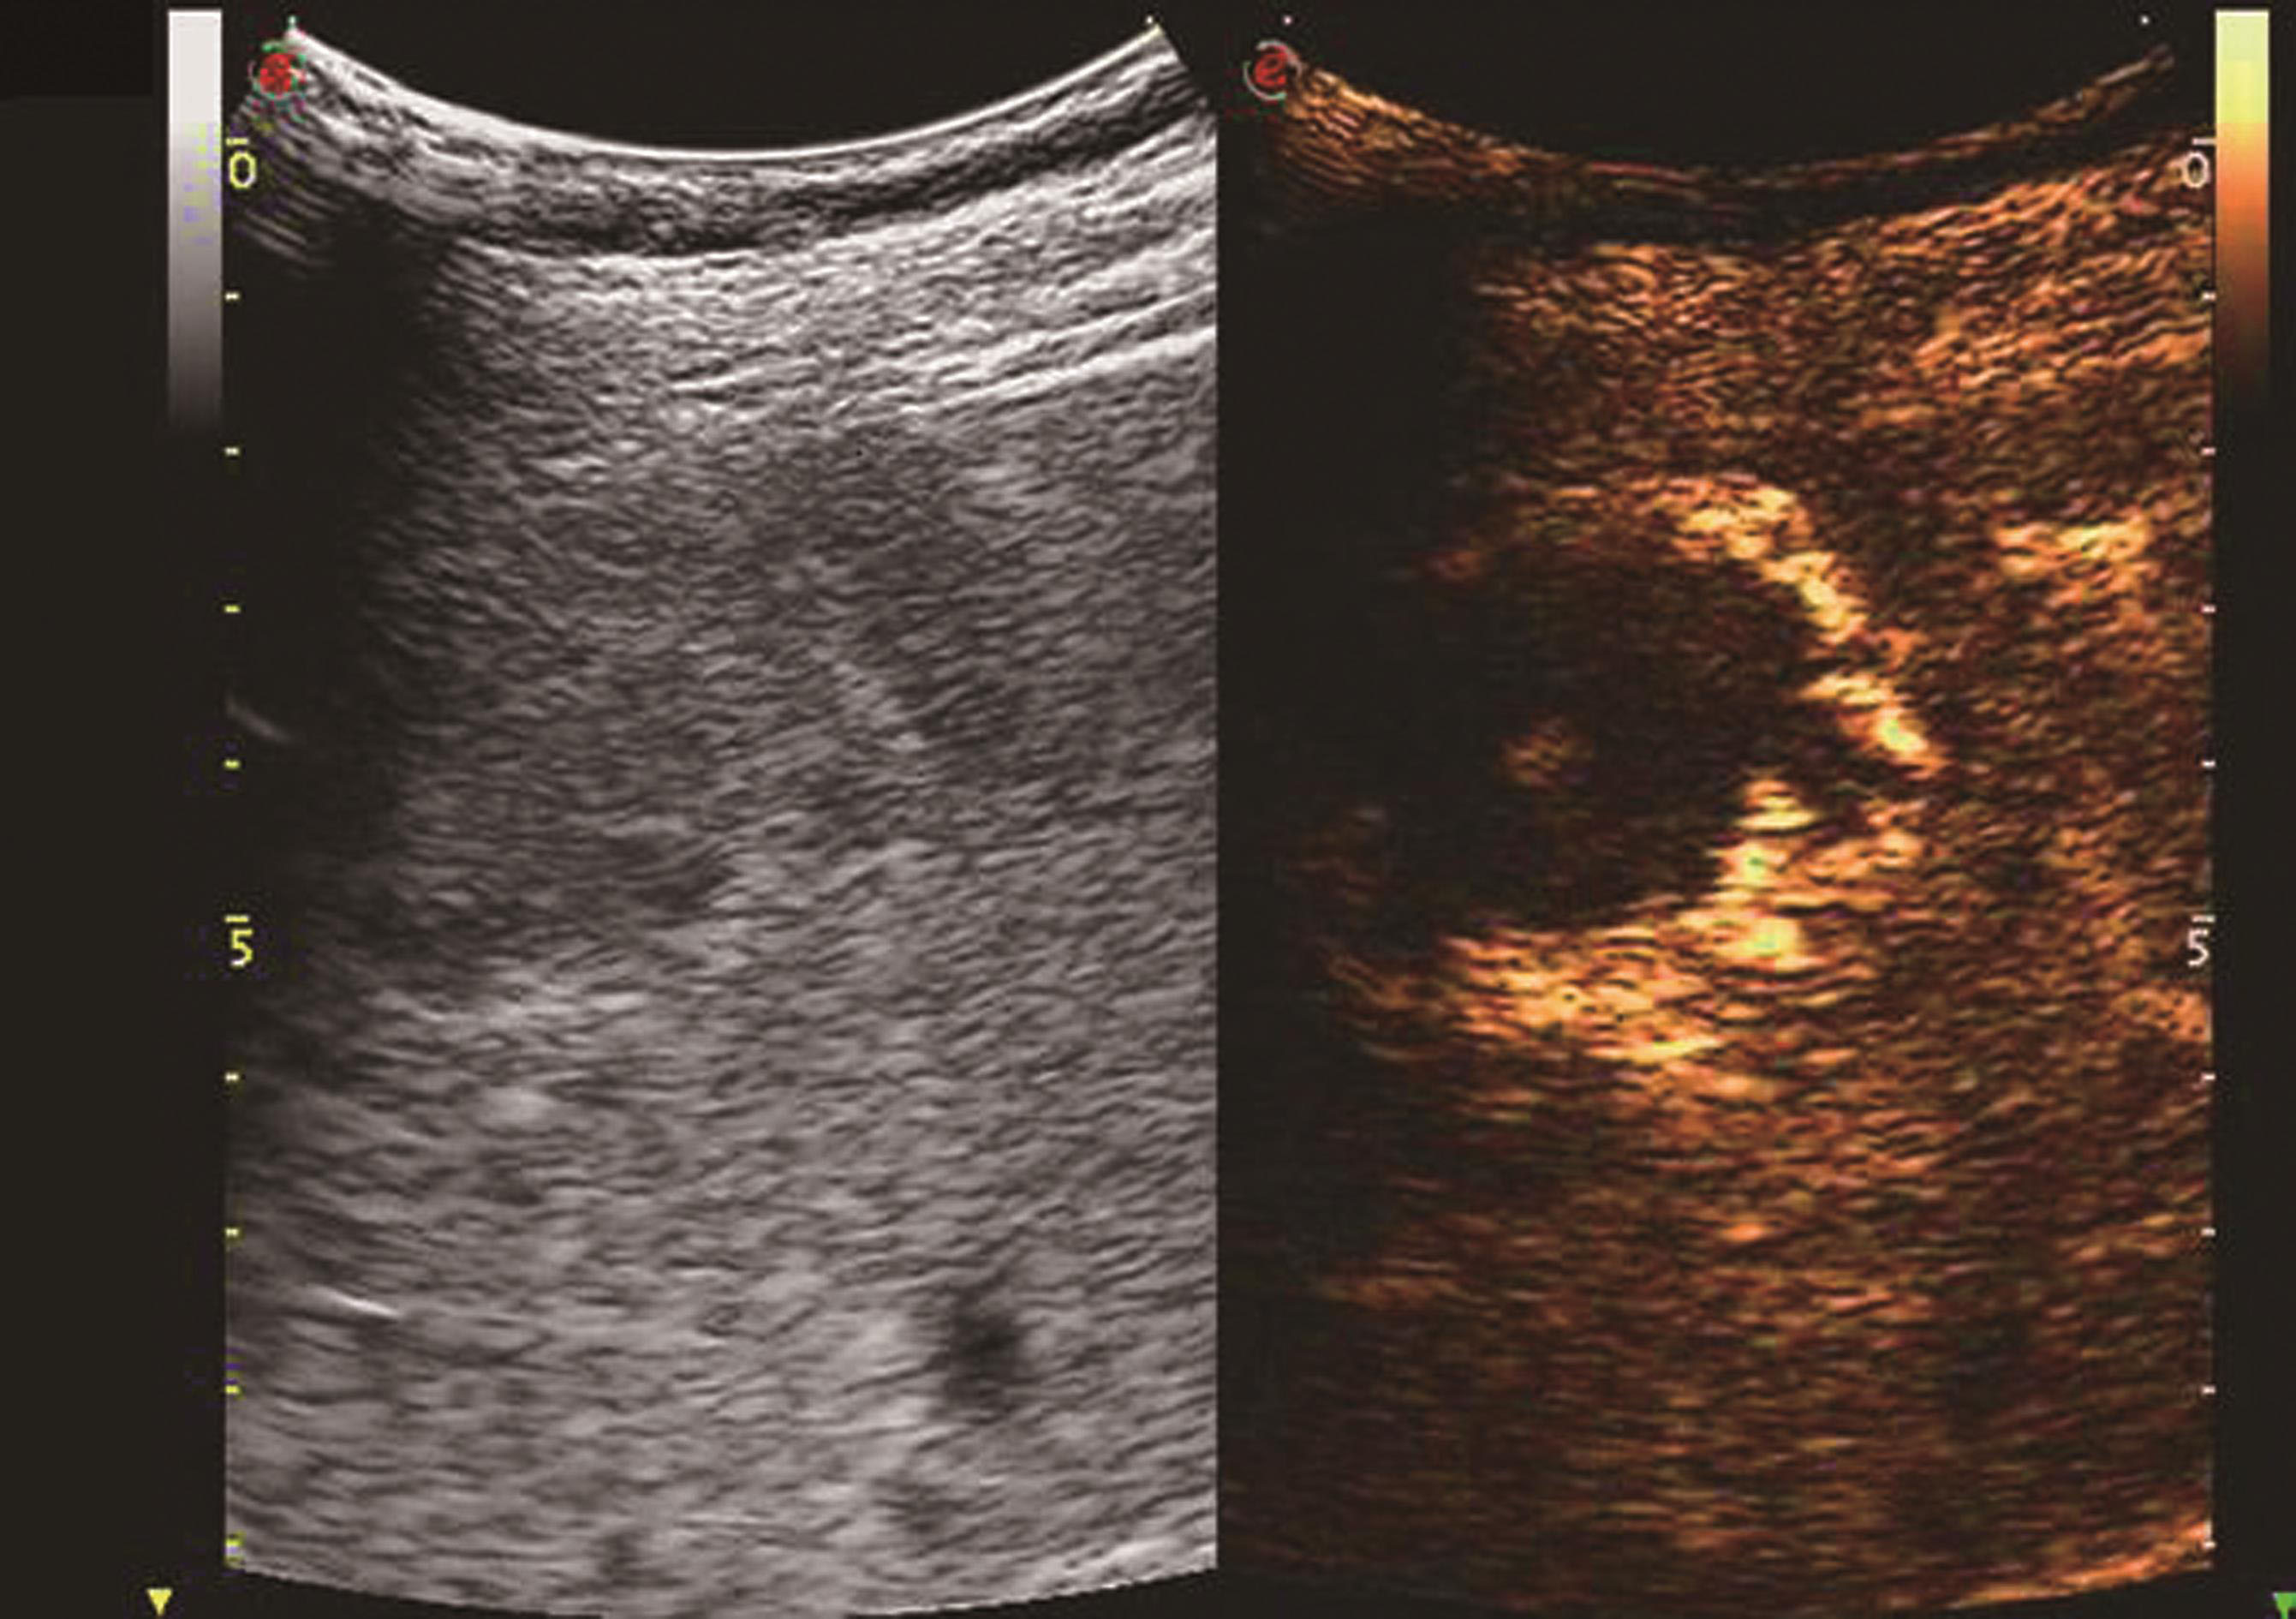

3.超声造影表现

炎症充血期,动脉期病灶整体快速蜂窝状增强,呈等增强或轻度高增强,无增强区呈细小点状无回声;脓肿形成期病灶内液性部分增大,动脉期呈簇状、蜂窝状或片状无增强区,脓腔后期成熟后可形成较大脓腔,超声造影可见不规则分隔带或“花瓣”征,实质部分门脉期及延迟期呈等增强,少数病例可轻度消退;脓肿恢复期,超声造影显示脓腔缩小,表现与脓肿早期类似,直至恢复正常。肝脓肿超声造影动脉期、静脉期及延迟期超声像图表现如图5-21-9~图5-21-11所示。

图5-21-9 肝脓肿超声造影动脉期

图5-21-10 肝脓肿超声造影静脉期

图5-21-11 肝脓肿超声造影延迟期